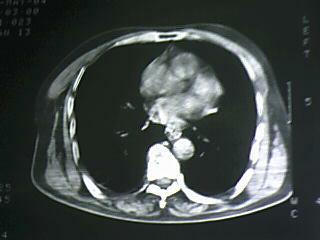

标题: CT19768:男 61岁 胸痛 咯血 一周。无发烧、无结核病史。 [打印本页]

标题: CT19768:男 61岁 胸痛 咯血 一周。无发烧、无结核病史。

右下肺中心型肺癌

纵隔窗图像不佳,怀疑右下叶支气管有狭窄,来几张清楚的,暂考虑----感染性病变----抗炎后复查

考虑 右下肺感染性病变,建议抗炎后复查。

考虑右肺下叶感染性病变;建议抗炎治疗后复查。